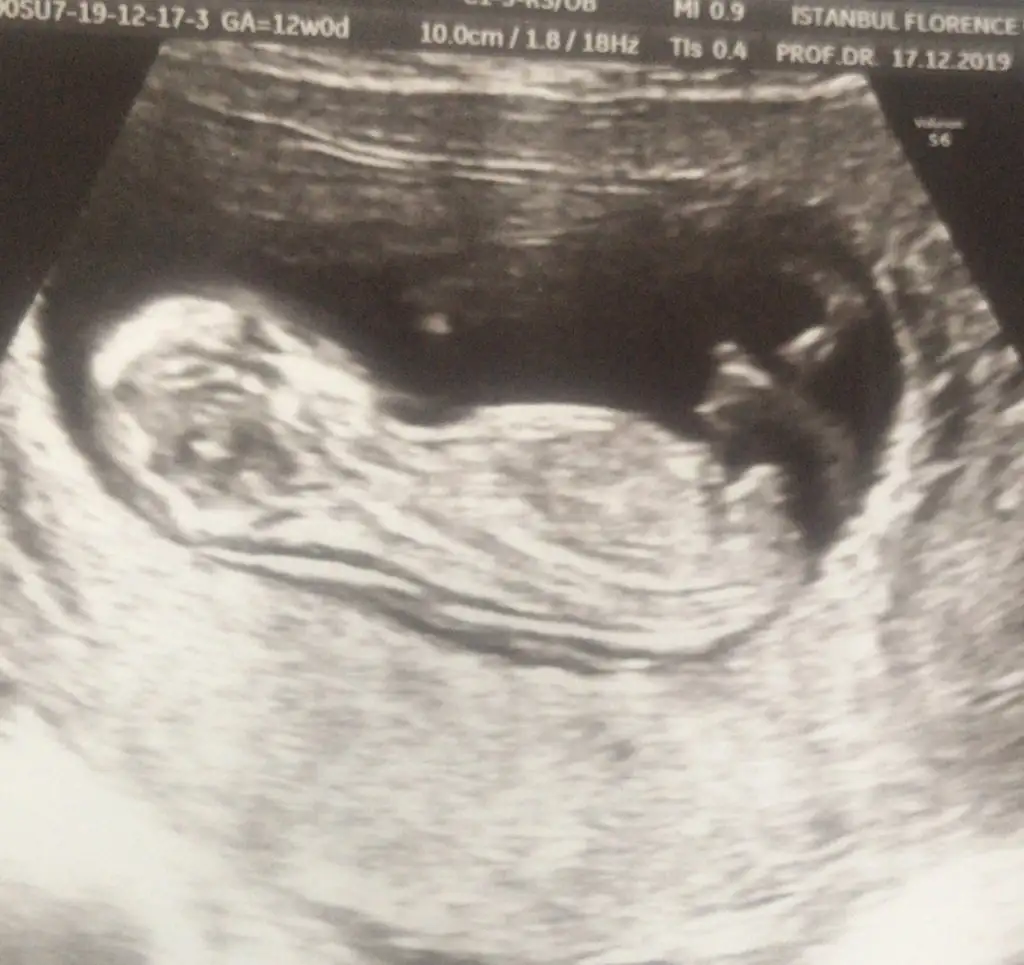

ErkekBunada bakarmisiniz 12 +2 haftalık cok merak ediyorum![]()

12+2 de kıza benziyor dedi. Başka bi tane de şu var ama pek net değil sanki.Başka usg varsa bakayım kaç haftalık usglerde tam detaylı bakamıyoruz dr daha iyi bakar biz usg de ne görürsek dr kaç haftslıkta kız dedi 11 yada 12 hafta olmalı usg nub içşn

Evet bu usgde kız paralel12+2 de kıza benziyor dedi. Başka bi tane de şu var ama pek net değil sanki.